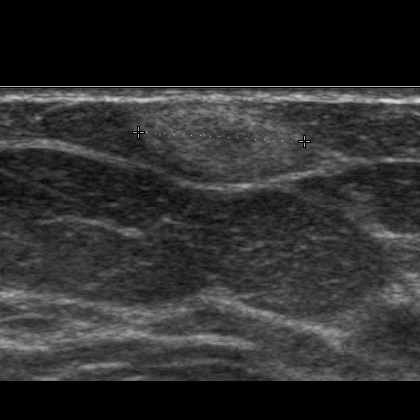

Drüsenkörper: ACR-Kategorie 3